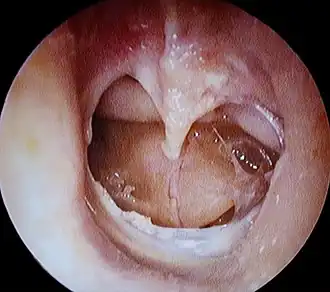

Galerie pathologie

tympanosclérose du tympan droit.

Large perforation du tympan gauche.

Perforation tympanique droite :

1) Tympanosclérose 2) Manche du marteau 3) Tête de l’étrier.